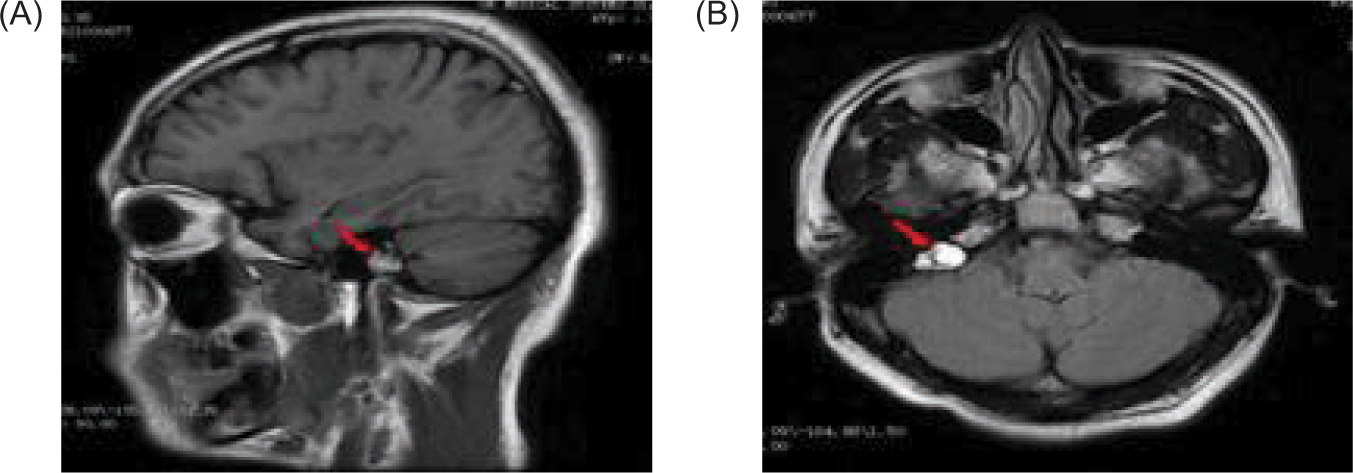

Figure 3: A magnetic resonance imaging (MRI) of the cranial reveals a possible mass in the right temporal bone jugular foramen, with a cross-sectional area of approximately 12×18 mm (red arrow); (A) sagittal position, and (B) flair view.

Figure 6: Magnetic resonance imaging (MRI) of the brain reveals a cystic mass in the right cerebellar hemisphere, approximately 40 mm in size (red arrow); (A) sagittal position, and (B) flair view.